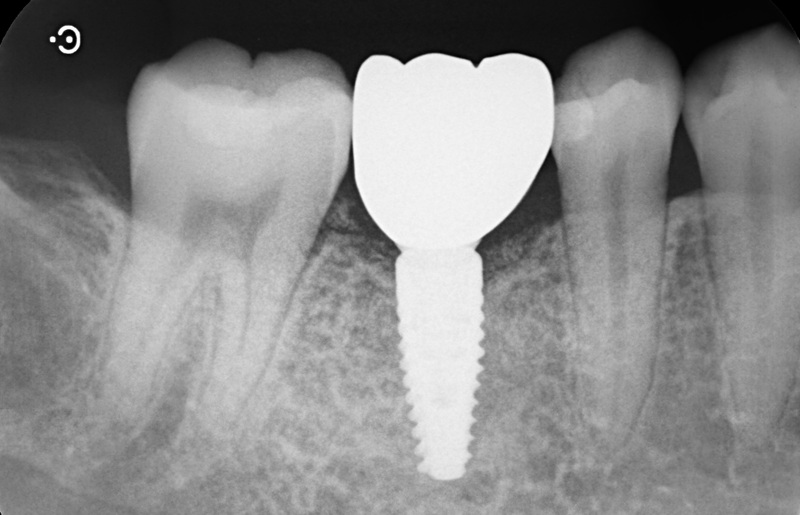

| 治療名 | GBRとインプラントを行った症例 |

| 治療説明 | インプラントを埋入予定の部位において、骨の吸収が見られたため、インプラント埋入と同時に小規模な骨造成(GBR)を行いました。治癒期間を経て、最終的にセラミックの上部構造を装着し、自然な見た目としっかりとした噛み合わせを回復しました。 |

| 治療回数・期間 | 6ヶ月 |

| 副作用とリスク | インプラント治療は、入れ歯やブリッジに比べて治療期間が長くなる傾向があります。骨造成が必要な場合は、さらに治療期間が延びることがあります。 また、手術後には一時的な違和感や痛み、腫れ、出血などが生じる場合がありますが、通常は2日〜1週間ほどで落ち着きます。 |

| 料金(税込) | GBR〈小規模骨造成〉:110,000円 インプラント一次手術:220,000円 二次手術:55,000円 上部構造〈セラミック〉:165,000円 合計:550,000円 |